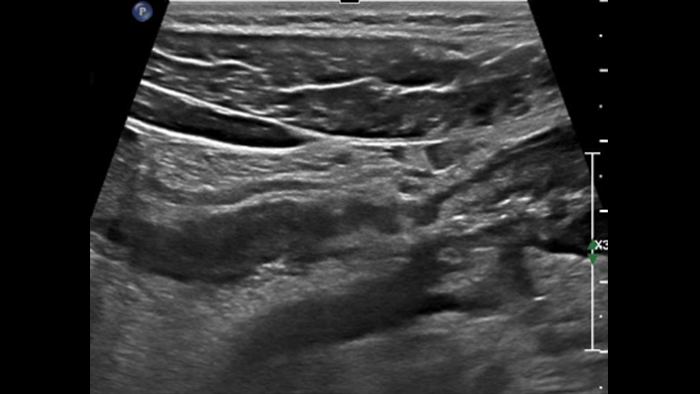

Ces images précises des lésions des couches pariétales forment la base de l’interprétation des changements induits par l’inflammation des parois intestinales et par conséquent de la différenciation entre la maladie de Crohn et la rectocolite hémorragique. L’exploration avec la technologie MFI (MicroFlow Imaging) constitue la deuxième étape. Il s’agit de reconnaître l’aspect de l’hypervascularisation induite par des épisodes inflammatoires actifs. La paroi intestinale normale semble comporter peu de microvaisseaux détectables, uniquement à l’interface de la muqueuse et de la sous-muqueuse, et dans le tissu adipeux mésentérique adjacent. Inversement, la paroi inflammatoire présente de nombreux microvaisseaux. La distinction entre les images d’artefacts de mouvement et les microvaisseaux circulants est alors un point essentiel nécessitant un ajustement parfait des paramètres de détection des micro-flux (voir les boucles, diapositive 8). La comparaison des 4 images suivantes de la maladie de Crohn met en évidence des différences claires qui devraient être interprétées comme étant représentatives des différents états inflammatoires. L’image 1 ne comporte aucun vaisseau visible, ce qui correspond probablement à une absence d’activité. L’image 2 présente quelques vaisseaux ; nous pouvons en conclure que cela correspond à une activité modérée. L’image 3 comporte un plus grand nombre de vaisseaux, signe probable d’une activité intense. L’image 4 présente encore plus de vaisseaux de type pulsatile, ce qui évoque probablement une activité très intense.

Les images sont absolument différentes selon l’état inflammatoire. C’est une question de densité, de pulsatilité, mais également de localisation des vaisseaux. C’est l’avantage de la superposition des images de micro-flux à celles des couches pariétales obtenues par échographie haute résolution. Sur les images suivantes, accompagnées des clichés d’IRM correspondants, il semble que dans le premier cas, à savoir une maladie de Crohn d’apparition récente, les vaisseaux soient localisés à la surface de la paroi intestinale, probablement au niveau de la muqueuse. En revanche, dans les autres cas de maladie plus avancée, ils sont également plus visibles à l’intérieur de la sous-muqueuse et dans le tissu adipeux adjacent.